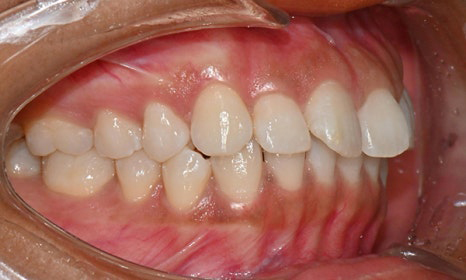

장치 착용 2달 후 사진 (2025.6)

교정을 시작하고 두 달 뒤,

8번째 장치를 착용하고 있을 때 찍은 사진을 보면

치아 배열도 많이 좋아졌고, 공간도 거의 닫혔어요.